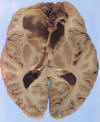

Anterior cerebral artery: Infarction due to blockage of anterior cerebral artery (ACA) typically lead to infarction along the midline extending from the frontal tip and along the cingulate gyrus.

Click on this icon to see the image of a case of bilateral anterior

cerebral infarction. This infarct was resulted from blockage of

bilateral anterior cerebral artery. |